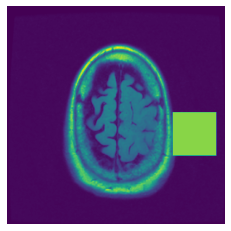

(a) Original

(b) Intelligent-Masking

(c) Context Prediction

(d) Context Restoration

Figure 3: More qualitative examples of different distorting strategies including our method. We show the different self-supervised mechanisms on both datasets of MR (rows: 1-3) and ultrasound (rows: 4-6) images for lower-grade glioma and breast cancer diagnosis respectively. We include both images of normal (rows: 1,4) and cancer (rows: 2,3,5,6) conditions for each dataset. We also observe that our method treats each image based on its context information with no predetermined strategy.